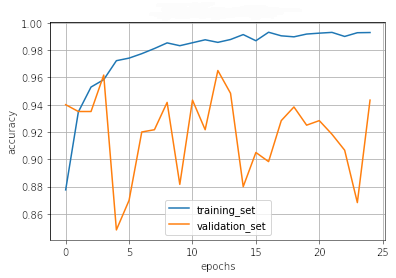

III.2 Classification results

The training procedure in all scenarios has converged. Looking at the evolution of training and validation accuracy (Fig. 11a) indicates that a larger validation dataset would be beneficial. To stabilise the classifier training a procedure of multiple training runs to select the best model is used (Materials and methods). Resulting classifiers are able to discriminate between classes with good precision, for example, see the confusion matrix of the best overall model presented in Fig. 11b. It can also be seen that for the normal class, the rate of misclassified images as COVID-19 ones is higher than for other classes. This effect is present for all models although smaller for the ones based on the EfficientNet-B0 architecture. In addition, the EfficientNet-B0 variants excel if the correct classification of viral pneumonia class images with the smallest rate of errors. However, the EfficientNet-B0 GAN augmentation scenario shows increased misclassification of healthy images which leads to a poor performance. The evolution of the training accuracy as well as confusion matrices for all models are summarised at the end of this section.

Training results for the two architectures are summarised in Figs. 13, 14, 15, 16, and Table 3. For each architecture four scenarios are considered as described in Training process part of the Materials and methods Section.